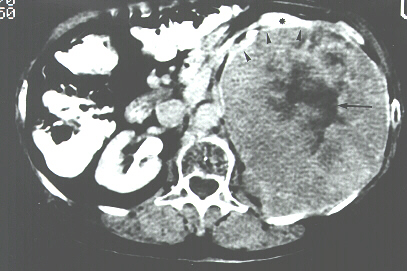

Fig. 3. Imagen de TC con contraste en la que se puede observar la gran tumoración renal izquierda bien delimitada (cabezas de flecha), con áreas de necrosis en su interior (flecha) y con muy escaso parénquima renal restante (asterisco). |